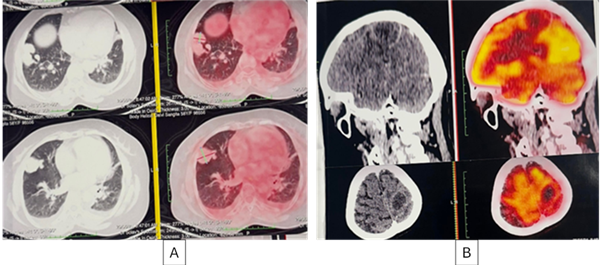

On PET

CT, the right lung showed weakly metabolic enhancing soft tissue lesion in the lower

lobe measuring 33 x 25 mm and 23 x 18 mm & an enhancing pleural based

lesion measuring 36 x 29 mm in the right middle lobe. The brain lesion was

ametabolic, confirming it to be an abscess (Figure 2).

Figure 2: (A)- Axial PET CT image shows weakly metabolic

enhancing soft tissue lesion in right lung lower lobe.

(B) -

Brain lesion appears ametabolic, confirming it to be an abscess